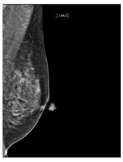

| ACR Class | Feature | Tissues Proportion | Example |

|---|---|---|---|

| C | Heterogeneously dense | 50–75% dense tissue | ![]() |